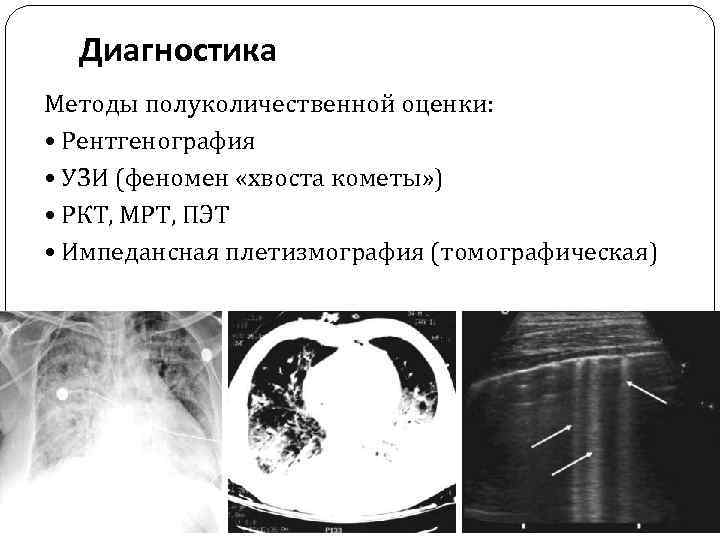

Диагностика Методы полуколичественной оценки: • Рентгенография • УЗИ (феномен «хвоста кометы» ) • РКТ, МРТ, ПЭТ • Импедансная плетизмография (томографическая)

Диагностика Методы полуколичественной оценки: • Рентгенография • УЗИ (феномен «хвоста кометы» ) • РКТ, МРТ, ПЭТ • Импедансная плетизмография (томографическая)